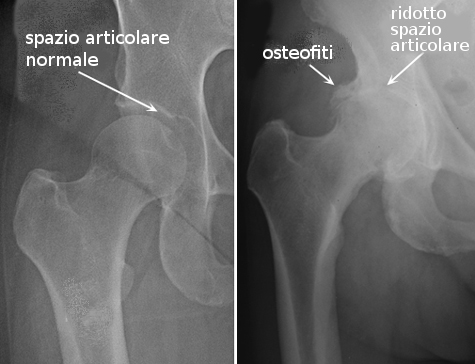

La protesi d'anca viene impiantata quando sia presente una importante sintomatologia dolorosa all'articolazione coxo-femorale, in presenza di immagini radiologiche che mostrino la presenza di:

- artrite/artrosi: condizione per la quale uno stato infiammatorio acuto o cronico determina una alterazione delle cartilagini articolari ed una riduzione dello spazio articolare, con formazione di osteofiti.

La sintomatologia varia molto da persona a persona ed è una sintomatologia periodica. Solitamente l'ortopedico prescrive esami radiologici di vario genere, come RNM e TC prima di indicare l'intervento di sostituzione totale dell'anca.